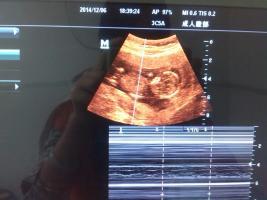

谁能帮忙看B超图片,以下是孕40天与孕13周照的B超图,现在是二胎压力大啊,请帮忙看看吧 点击展开 匿名用户 2014-12-08 10:29 为您推荐: 其他回答 从B超单子上是看不出男女的,只有在B超的照射下才能看到生殖器官,才能分辨出男女。 ok天秤座10 2014-12-08 21:03 相关问题 为什么23周照的彩超没有彩色图片呢,而是和刚怀孕的时候照的B超一样子是一张A4纸打印出来的呢! 什么样B超图长形和圆形怀孕图片 怀孕64天了,是二胎,做了二次B超,54天和61天时做的,只发现胎芽,却没有心管搏动,也没见红的